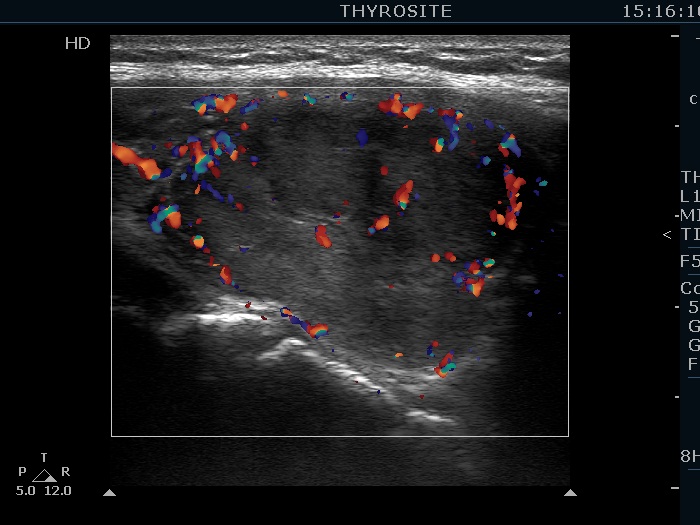

Consecutively operated patients with autoimmune thyroid disease - case 16 (50) (ultrasonographic picture 9)

Left lobe, longitudinal view, power Doppler mode. The nodule shows sign of perinodular vascularity, as well.